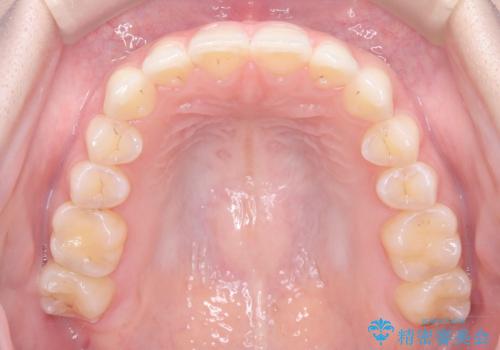

- 前歯のガタガタが気になるとのことでご相談いただきました。診察すると、歯列のスペースが不足し、前歯が重なっている状態でした。抜歯をせずに整えるため、歯と歯の間をわずかに削るIPR(歯列幅径削除)と、奥歯を後方へ動かす遠心移動を組み合わせてスペースを確保しながら並べる治療計画を立てました。

インビザラインを用いて歯を少しずつ移動させながら、IPRで微調整を行い、スペースを確保しました。また、奥歯を遠心移動させることで、前歯を自然な位置に並べることができました。治療後は、「ガタガタがなくなり、スムーズな歯並びになった」と患者様にもご満足いただきました。